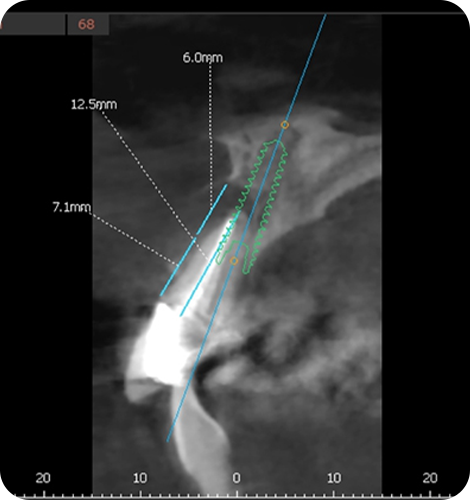

ただし、全てのケースで適応できる訳ではなく、術前の模型やレントゲン、CT検査による診断が必要です。